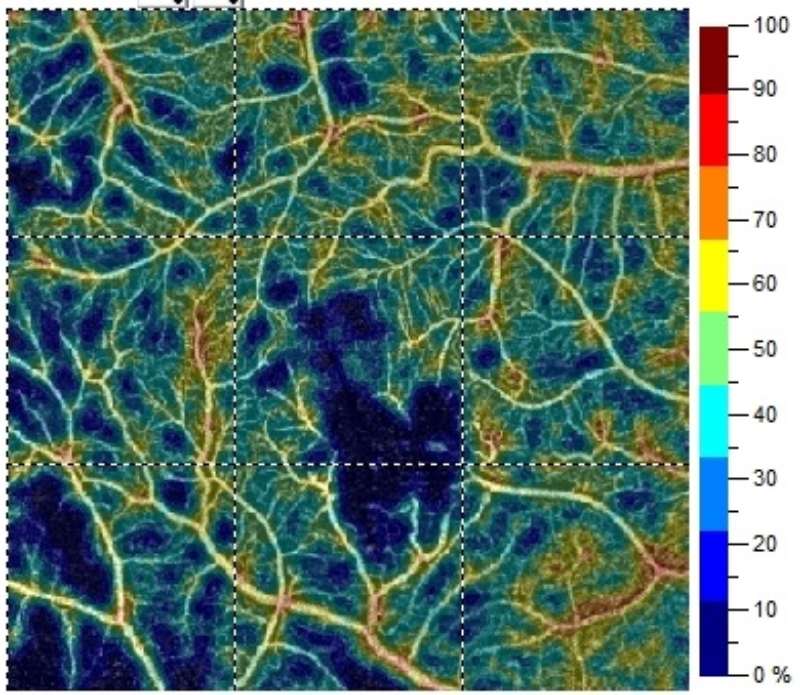

AngioAnalytics™ allows you to measure foveal avascular zone (FAZ) parameters, areas of abnormal flow in the outer retina and choroid, and vessel density of the superficial vascular complex, deep vascular complex and radial peripapillary capillaries. Multi scan analysis enables assessment of visit-to visit change, and trend reports predict change over time to bring powerful new information to your daily clinical practice.

AngioVueHD produces high-density scans with 73% more sampling points* to give you a 6x6mm scan with outstanding resolution. Now you can confidently evaluate fine vessels extending beyond the central 3x3mm region of the macula. Automatic montage (shown at right) expands the field of view even further by instantly combining macula and optic disc images for a 10x6mm widefield view.

AngioVue® lets you see the retinal vessels in a whole new way. Three-dimensional images are separated into individual layers of retinal vasculature to show you an unprecedented level of detail and isolate areas of interest.